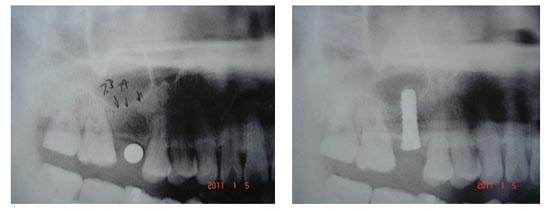

图(1) 图(2)

图(1)为上颌窦低

图(2)上颌窦内提升术上颌窦底象帐篷一样,完好无损地提升

上颌磨牙区缺失牙以后,传统上通常采用活动义齿和固定义齿两种修复方法。固定义齿对基牙要求较高且末端游离缺失的上颌磨牙不适合选择固定义齿修复,而活动义齿异物感强且咀嚼效率较低。这种上颌磨牙末端游离缺失适合选择种植牙修复,但此区又常由于先天性上颌窦底位置过低、牙槽骨严重吸收、萎缩等原因,使种植体易穿入上颌窦引起感染等并发症,导致种植失败。因此上颌窦内提升术将上颌窦底的粘膜象撑帐篷一样向上提升,并使之完好无损不破裂,这样可以增加上颌窦底垂直向的高度。扩大上颌后牙种植修复的适应证,解决因上颌窦底高度不足而导致的各种种植修复中的问题。